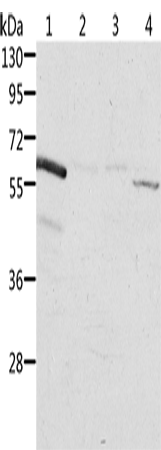

分类: 科研抗体货号: P07838别名: ALI1; DEGA; AMIGO-2应用: WB,IHC反应种属: Human, Mouse, Rat